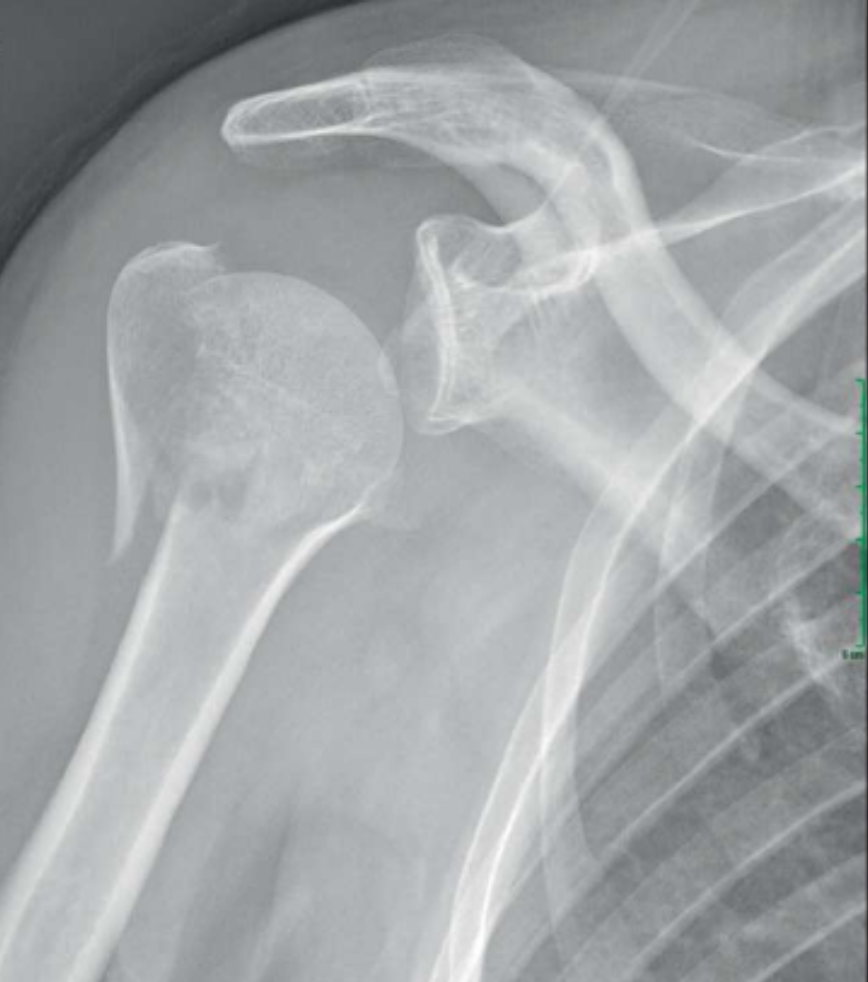

Une fracture de l’extrémité supérieure de l’humérus est une blessure qui se produit lorsque l’os de l’humérus, situé dans la partie supérieure du bras, se casse à proximité de l’articulation de l’épaule.

Bien que l’on parle « d’une » fracture, très souvent il y a plusieurs traits de fracture. Leur analyse, ainsi que les déplacements éventuels des fragments osseux, est capital pour décider de la meilleure prise en charge adaptée au patient et à son type de fracture.

Le diagnostic est fait en réalisant un bilan radiographique simple. Lorsque la fracture est confirmée, un bilan scanner sans injection est presque toujours réalisé actuellement. En effet, il permettra de visualiser les différents traits de fracture et le déplacement des différents pièces osseuses avec précision. De cette analyse découle la prise en charge de cette fracture.